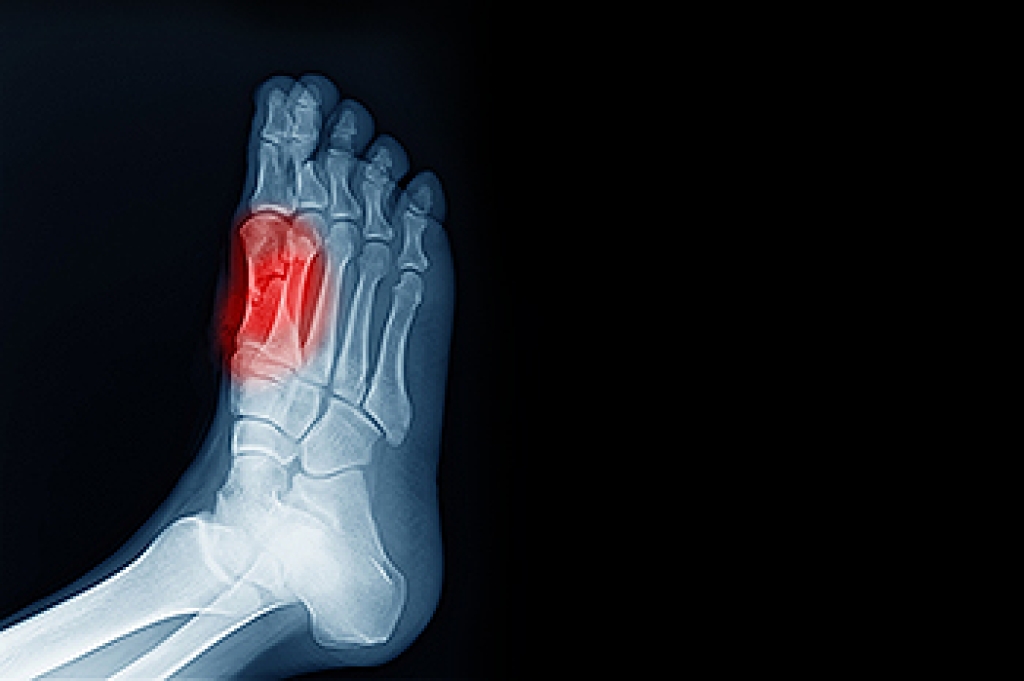

The pain associated with spurs is often because of weight placed on the feet. When someone is walking, their entire weight is concentrated on the feet. Bone spurs then have the tendency to affect other bones and tissues around the foot. As the pain continues, the feet will become tender and sensitive over time.

There are many ways to treat heel spurs. If one is suffering from heel spurs in conjunction with pain, there are several methods for healing. Medication, surgery, and herbal care are some options.